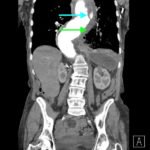

The patient’schest X-ray revealed a prominent mediastinum and opacification in the left middle and lower lung fields. The CT showed an aortic aneurysm extending from the thorax to the abdomen with rupture near T7 (blue arrow). It also showed periaortic hemorrhage with active extravasation (green arrow) likely secondary to a penetrating ulcer and bilateral pulmonary opacities concerning for hemothorax (pink arrow).